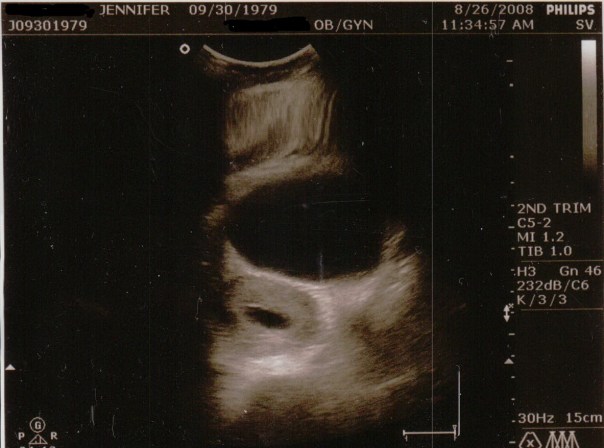

The first two images were during the regular abdominal ultrasound. The sac is the dark ovular hole on the left. The larger hole above it I believe is my bladder.

The next day by the time I was at the drs at 11:30am the bleeding had stopped entirely and my pad was completely clean. We went in for the ultrasound on Tuesday August 26 when I should have been 11 weeks 3 days along according to my LMP. I could barely move because I had to pee so bad so the tech told me she’d take a quick look and then have me empty. She did the abdominal ultrasound and said that I did a great job filling up my bladder (yippy, do I get a gold star?!), she pointed out the sac and said that we’d have to go internally to see the baby because it’s still so small.